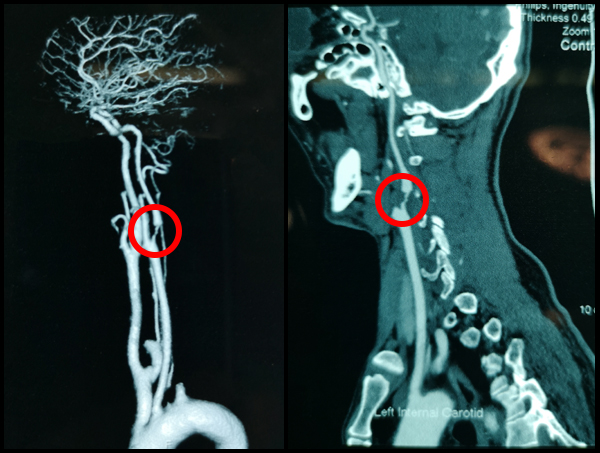

梗塞在刘先生左侧颈动脉的斑块

刘先生的左侧颈动脉CTA